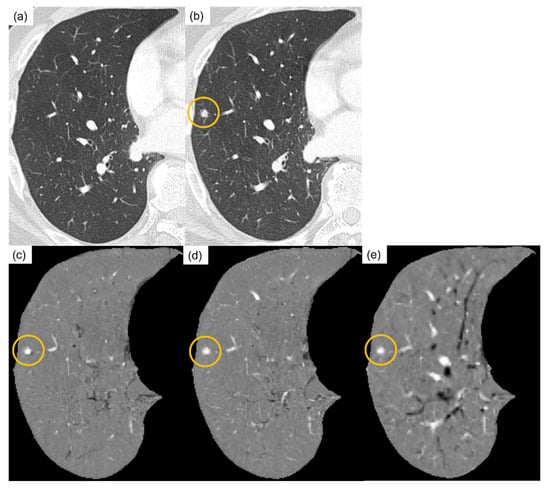

3.1. Temporal Subtraction Technique with Deep Neural Network

4.2. Results and Evaluation